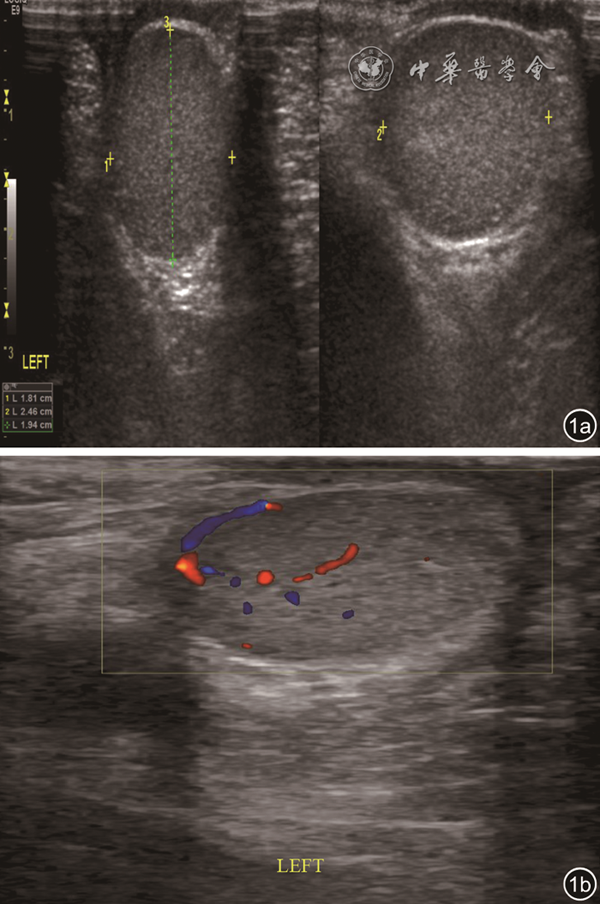

患儿,男性,7岁,因发现左侧阴囊内无痛性包块1 d于2021年1月到成都市妇女儿童中心医院就诊,否认阴囊外伤及感染病史。体格检查:左右阴囊不对称,左侧阴囊内触及一包块,大小约3 cm×2 cm×1 cm,质硬,表面稍凹凸不平,活动可,边界清楚,无触痛。双侧腹股沟区近阴囊处可扪及睾丸样物,牵拉后可置于阴囊,松手后立即回缩。实验室检查:甲胎蛋白19.3 ng/ml、铁蛋白1.4 ng/ml。超声检查所见:左侧阴囊内查见一卵圆形回声团,大小约2.4 cm×1.8 cm×1.9 cm,边界清楚,形态规则,实质回声不均匀,以等回声为主,可见散在沙砾样钙化(图1a);彩色多普勒血流成像(color Doppler flow imaging,CDFI)显示病灶内部较丰富血流信号(图1b);频谱多普勒可测得动脉及静脉频谱;双侧腹股沟中份查见睾丸样回声;双侧腹股沟区可见淋巴结样回声。超声提示:左侧阴囊内实性占位,考虑睾丸肿瘤。CT检查平扫示:左侧阴囊内侧见一类圆形混杂密度灶,脂肪密度为主,CT值约-37HU,其内见点状稍高密度影,病灶边界尚清(图2a);增强扫描其内见絮状轻度强化影(图2b)。遂行左侧阴囊内肿物切除术,术中发现左侧睾丸位于同侧腹股沟区,左侧阴囊下极可见一椭圆形包块,大小约3 cm×2 cm×1 cm,质硬,表面光滑,活动可,边界清楚,与精索近端稍粘连,右侧睾丸位于同侧腹股沟区。术后病理结果:肿瘤界清,小叶状或片状排列,瘤细胞类圆形或多边形,胞膜厚,胞浆丰富,嗜伊红,颗粒状,呈细小的多空泡状,核小而圆,深染、居中(图3)。免疫组化结果:S-100(+)(图4)。最终诊断:冬眠瘤。术后随访1个月,患儿一般情况良好,未见肿瘤复发。

图1 左侧阴囊冬眠瘤超声图像。图a为二维超声示边界清楚的卵圆形肿块中见散在沙砾样钙化;图b为彩色多普勒血流成像示肿块内部较丰富血流信号

超声是诊断儿童体表包块的首选影像学检查方法,除观察包块的边界、回声、血供外,还可了解周围毗邻关系。文献报道139, 10, 11, 12冬眠瘤缺乏典型的超声特点,二维超声可表现为边界清楚的低回声、等回声亦或高回声肿块,肿块内部回声可均匀或不均匀,由于棕色脂肪组织内含有较丰富的毛细血管,因此CDFI显示肿块内血流信号较丰富。本例患儿以阴囊包块就诊,分析超声误诊的原因如下:(1)儿童阴囊内肿物常以畸胎瘤、卵黄囊瘤、白血病及淋巴瘤导致的睾丸浸润、副中肾管囊肿等疾病多见,本病实属罕见,易被超声医师忽视;(2)本例患儿以无痛性症状就诊,触诊时包块质地较硬;(3)超声声像图示实性肿块中见散在沙砾样钙化,且CDFI显示病灶内部较丰富血流信号,双侧腹股沟区可见淋巴结样回声,上述表现使得超声提示倾向于睾丸肿瘤。